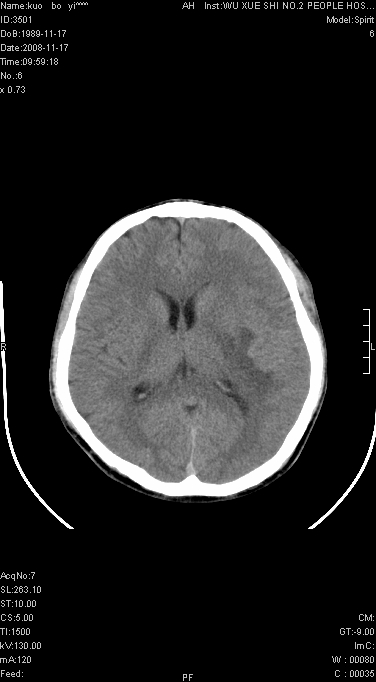

增强已传.年龄19岁.请会诊

增强后水肿中心高密度灶有明显强化,强化不均匀,呈雪花状或絮状,且强化明显,若为肿瘤,应该出现形态较规则的瘤体影,强也有例外如胶质瘤就可以形态不规则.但胶质瘤明显强化者多为恶性间变性,与病史及相关表现太不相符.因此本例多考虑为炎症引起.

左顶叶较大范围水肿区,内见明显强化的片状 棉絮状组织,但占位效应不明显。多考虑:脑炎!

还是考虑原发脑胶质瘤,梗塞缺血水肿的低密度要同时累及皮、髓质并要符合动脉供血的区域分界特点,本例强化后见瘤体结节及向周围浸润生长的瘤血管都强化了,水肿广泛呈指状,占位效应使同侧脑皮质受压变薄、脑沟消失但因实质性的瘤体尚小所以中线无明显移位。不知各位同意这样分析吗?(转移瘤多为多处病灶)

首先考虑脑胶质瘤。有明显的左顶叶脑白质水肿,病变轻度占位效应,花环样强化,脑炎——影像不支持!